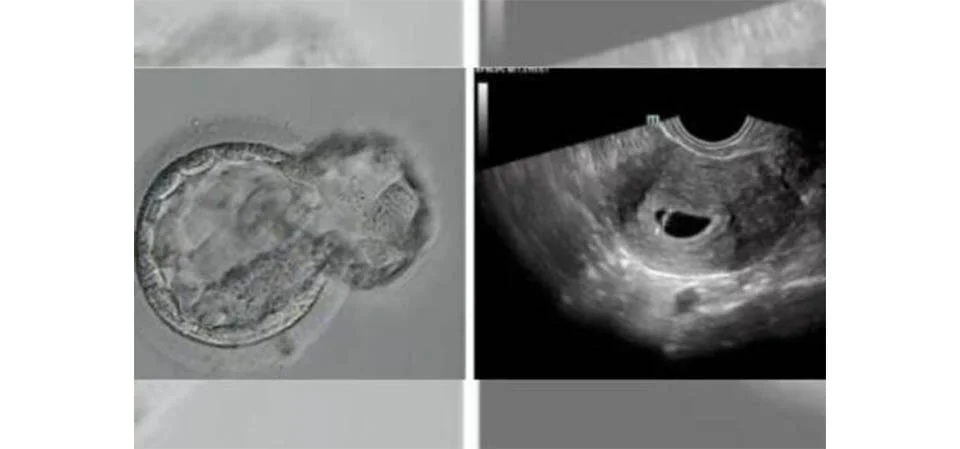

Um bebê saudável nasceu após ser concebido com uma técnica de fertilização totalmente automatizada e controlada digitalmente ⎯ um marco inédito na med...